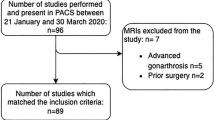

Patient recruitment, examination, and data acquisition for this prospective study were performed between May 2018 and May 2019. Eleven healthy volunteers (Group I; male and female) aged between 18 and 45 years were enrolled for reliability testing. Subjects in Group I had no history of knee injury or surgery and a standard clinical examination of the knee revealed no pathologic findings. Additionally, ten consecutive patients presenting for a follow-up (FU) examination (minimum 12 months FU) after anterior cruciate ligament reconstruction and all-inside lateral meniscal radial tear repair were asked for participation for validity testing (Group II). Lateral ME measurement is of high interest in patients undergoing radial meniscal tear repair since a correlation between lateral ME and radial meniscal tear healing is assumed [15]. Both knees were examined in all subjects, so that data of 22 and 20 knees were available in Group I and Group II, respectively (Fig. 1). In both groups, neutral leg alignment, clinically assessed using the methods described by Navali et al. [20] and Hinman et al. [21], was required for participation. Clinical signs of knee joint osteoarthritis [22, 23] as well as obesity (BMI ≥ 30) were criteria for exclusion. Lateral ME, measured under two loading conditions using US (Group I and Group II) and MRI (Group II only), served as the main outcome parameter.

Group assignment. a Reliability testing based on Group I. Ultrasound (US) images were acquired twice in an unloaded condition and once in a loaded condition by each observer. Intrarater reliability testing was based on repeated measurements in the unloaded condition. Interrater reliability testing was based on measurements taken by each observer in the unloaded and loaded condition. “n” represents the number of images acquired by each observer in the respective loading condition. b Validity testing based on Group II. US and MRI images were acquired in both knees of all subjects in the unloaded and loaded condition. “n” represents the number of images acquired for each imaging modality in the respective loading condition